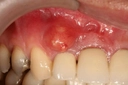

Diş ekimi, kaybedilen dişlerin yerine yapay dişlerin yerleştirilmesi işlemidir. Bu işlem, hem estetik hem de fonksiyonel açıdan birçok avantaj sunmaktadır. Diş ekimi, günümüzde diş hekimliği alanında en yaygın kullanılan yöntemlerden biri haline gelmiştir. Bu makalede, diş ekiminin faydaları detaylı bir şekilde ele alınacaktır. Diş Ekimi Nedir?Diş ekimi, kaybedilen dişlerin yerine cerrahi bir işlemle titanyum veya benzeri malzemelerden yapılan yapay diş köklerinin yerleştirilmesini içeren bir tedavi yöntemidir. Bu işlem, diş kaybının neden olduğu estetik kaygıları gidermenin yanı sıra, çiğneme fonksiyonunu da yeniden kazandırmaktadır. Diş Ekiminin Estetik FaydalarıDiş ekimi, hastaların gülümseme estetiğini önemli ölçüde iyileştirmektedir. Aşağıdaki avantajlar estetik açıdan dikkate değerdir:

Diş Ekiminin Sağlığa FaydalarıDiş ekimi, sadece estetik ve fonksiyonel avantajlar sunmakla kalmaz, aynı zamanda sağlık açısından da faydalar sağlar:

Diş ekimi, günümüzde oldukça yaygın bir işlem olmasına rağmen, her cerrahi müdahalede olduğu gibi bazı riskleri de beraberinde getirebilir. Enfeksiyon ve vücut reddi, bu işlemin potansiyel komplikasyonları arasında yer alır. Ancak, bu riskler uygun önlemlerle önemli ölçüde azaltılabilir.